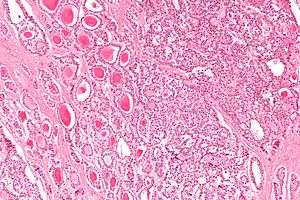

| Micrograph of a strumal carcinoid. H&E stain. | |

The strumal carcinoid is a type of monodermal teratoma with histomorphologic features of (1) the thyroid gland and (2) a neuroendocrine tumour (carcinoid).[1][2]